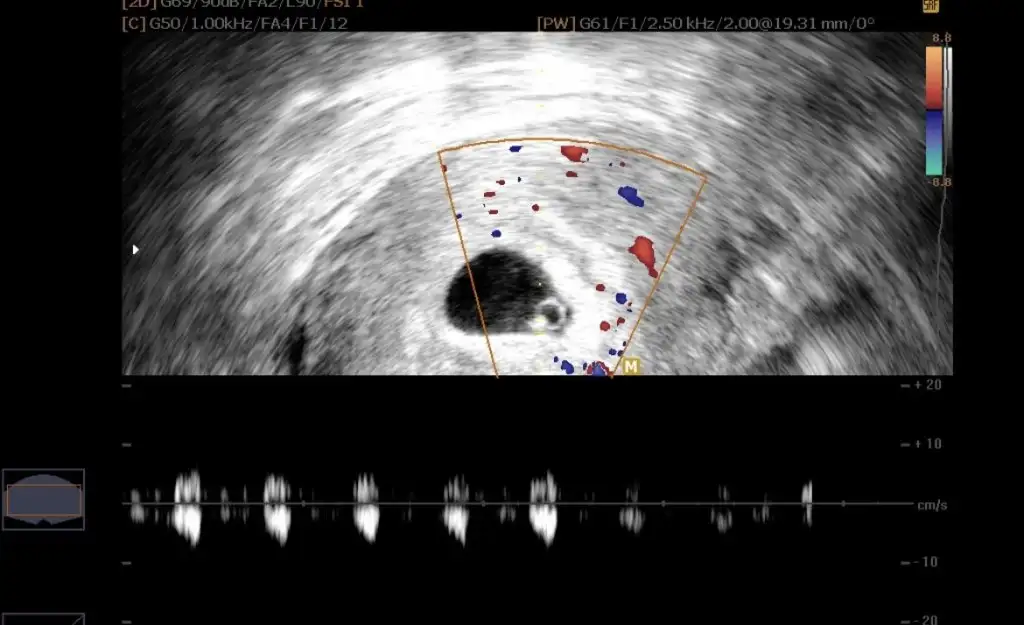

Erkek canım saglıkla gelsin inşallahEki Görüntüle 3244857 vajinal bakildi

Vajinal mi bakildi? Bebek daha embriyo oldugu icin vajinal daha rahat gorunuyor ve kalp atisi daha rahat duyuluyor bildigim kadariyla. Belki vajinal baktirsaniz daha net sonuc alirsinizKizlarrr

Yok karından ultrasondaVajinal mi bakildi? Bebek daha embriyo oldugu icin vajinal daha rahat gorunuyor ve kalp atisi daha rahat duyuluyor bildigim kadariyla. Belki vajinal baktirsaniz daha net sonuc alirsiniz

Vajinal bu arada söylemeyi unuttumSeninkide kız canım saglıkla gelsin inşallah![]()

Vajinal ise erkek kuzum saglıkla gelsin inşallah1 ay daha beklemeden tahmin alayım ben de bakarsanız sevinirim![]()